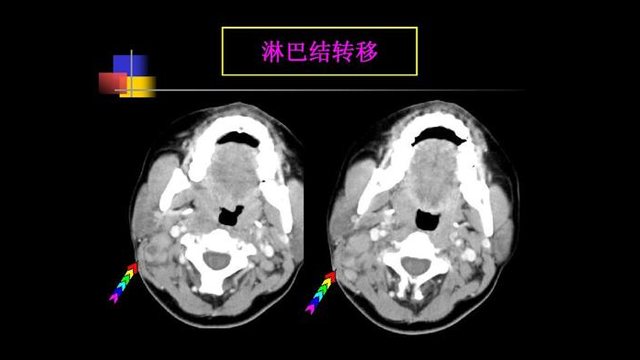

由于鼻咽癌发病的部位很隐秘,发病症状和其他良性疾病是很难鉴别的,而且大部分鼻咽癌患者确诊时都已处于中晚期。随着颈部淋巴结和远处转移,死亡率逐渐上升。